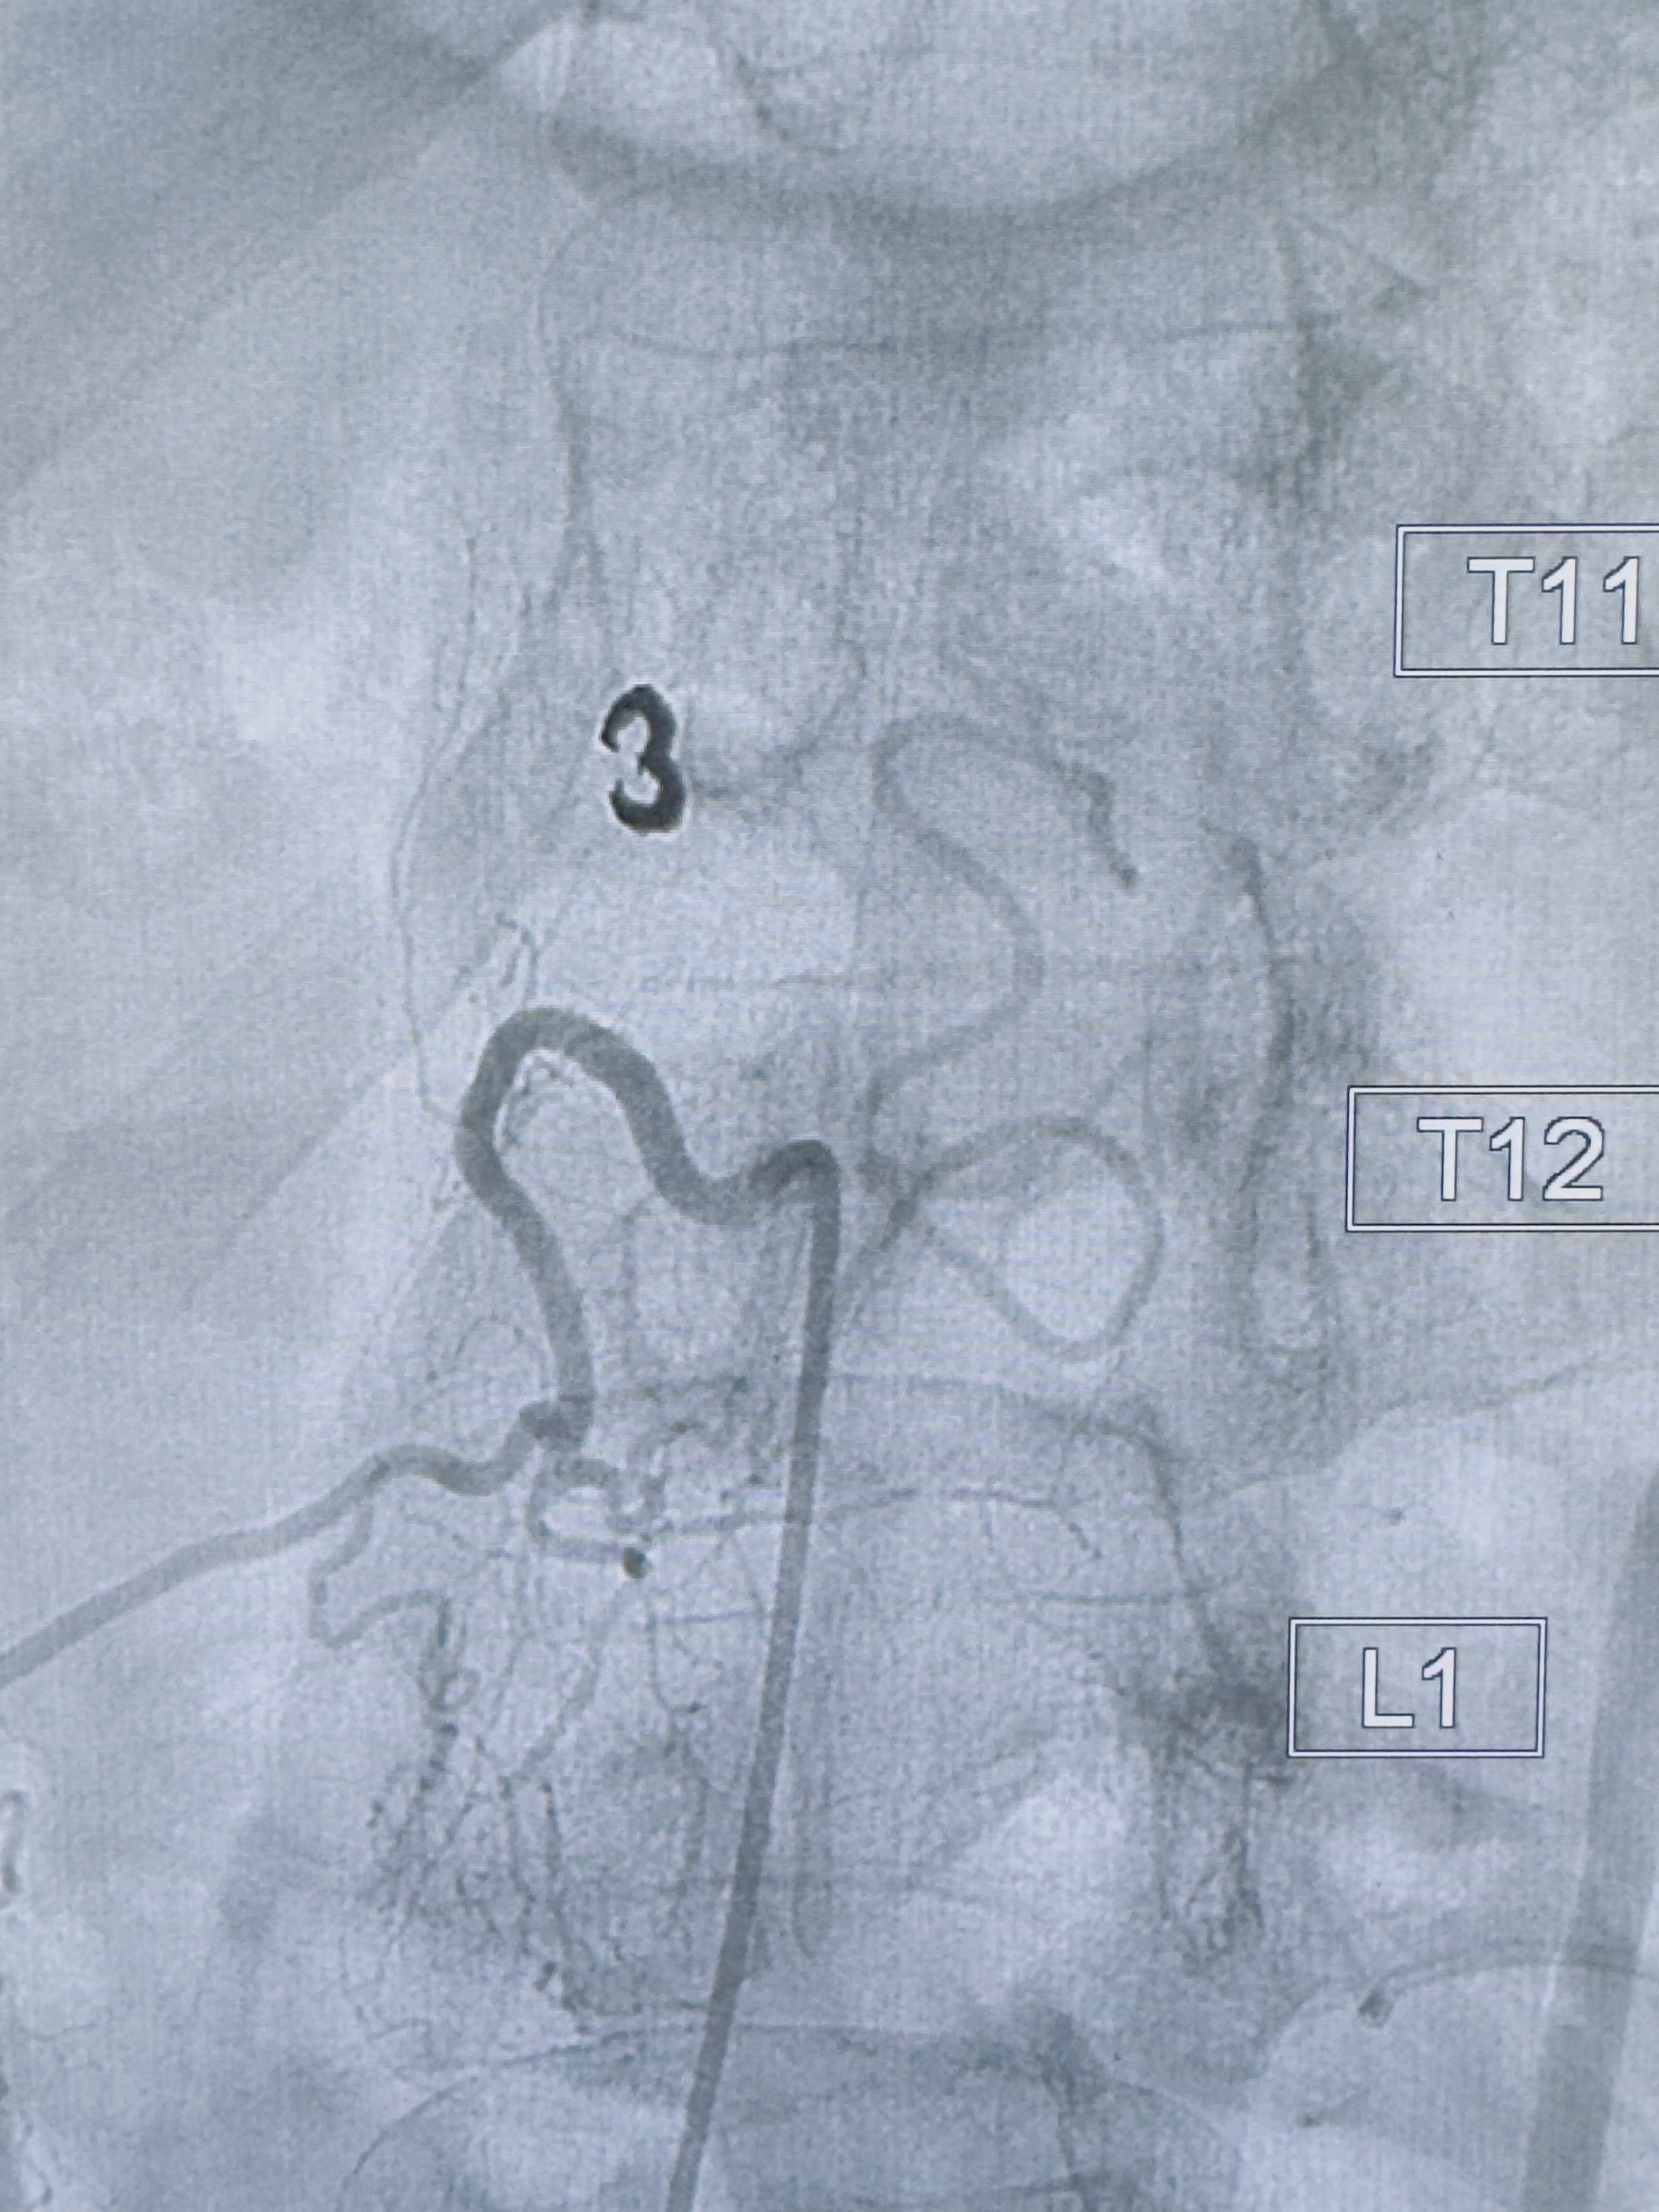

2023-10-13DSA:右侧L1水平硬脊膜动静脉瘘,供血动脉为右侧L1,附近动脉未见明确吻合供血,供血动脉处可见脊髓前动脉发出